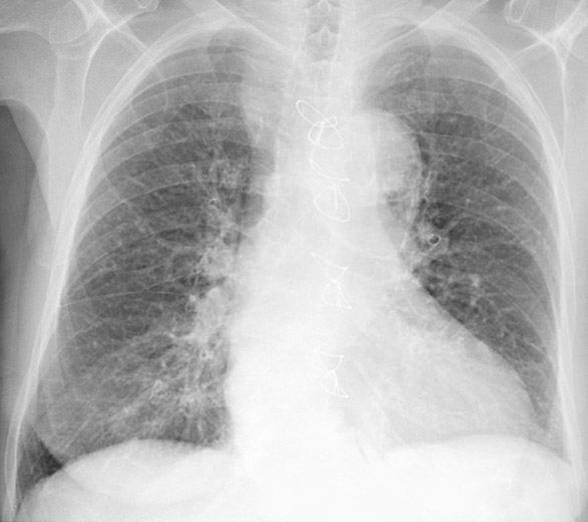

weekly clinical round for undergraduate from 8 to 11 AM during which interpretation of CHEST X rays was done for all cases of cardiothoracic surgery, gived by 2 staf member for 3 months